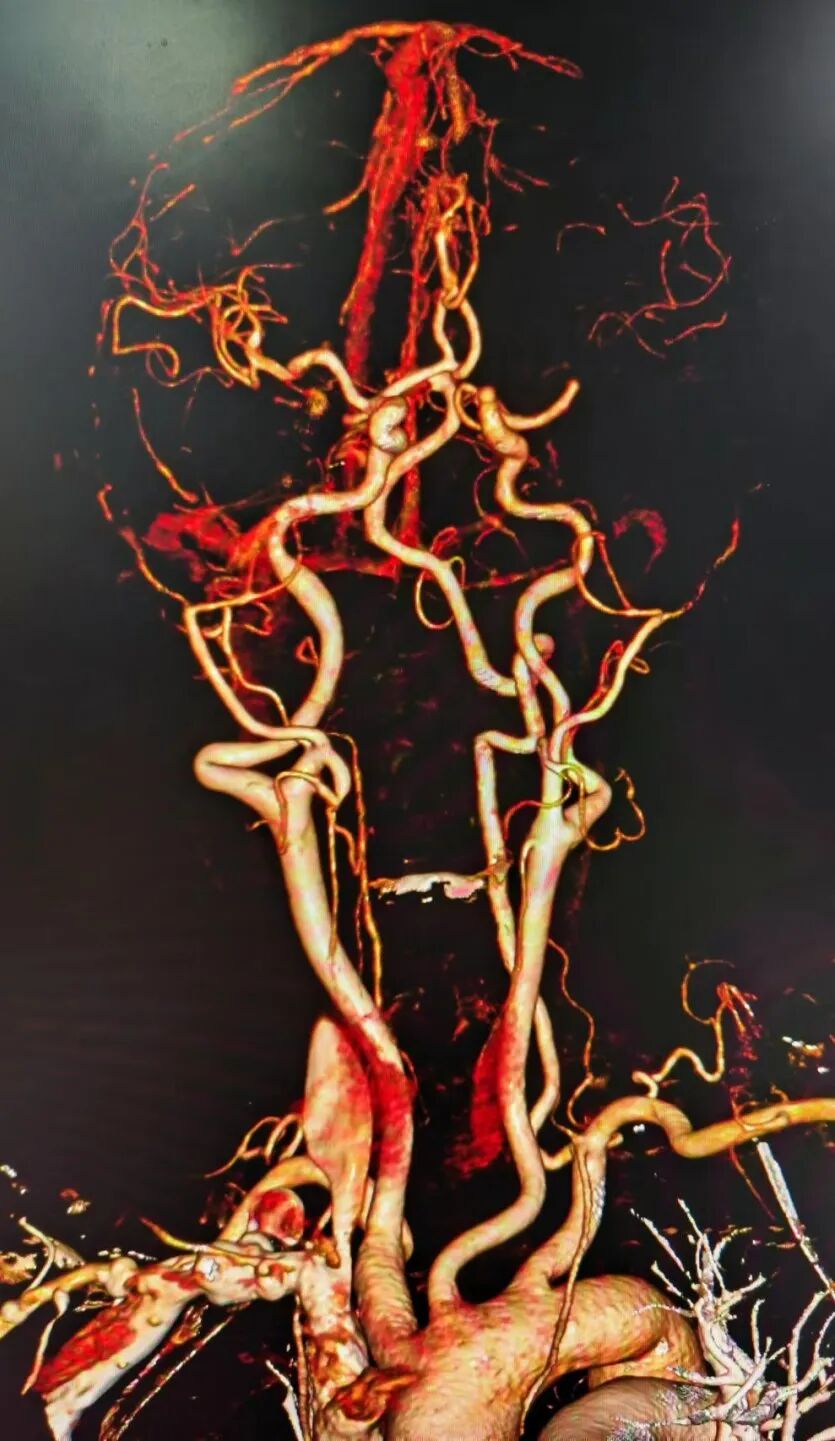

术前CTA提示左侧大脑中动脉M1段闭塞。

90cm Locaste 088输送导管建立路径,造影提示左侧大脑中动脉M1段闭塞。